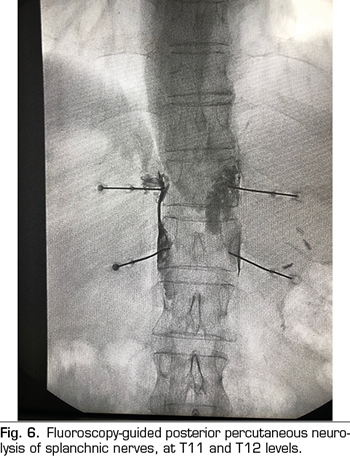

The percutaneous technique is performed using a retrocrural posterior approach, usually guided by fluoroscopy (Figure 6). The lesions can be performed by conventional radiofrequency or using neurolytic agents as in the celiac plexus.

Conventional or thermal radiofrequency of the splanchnic nerves